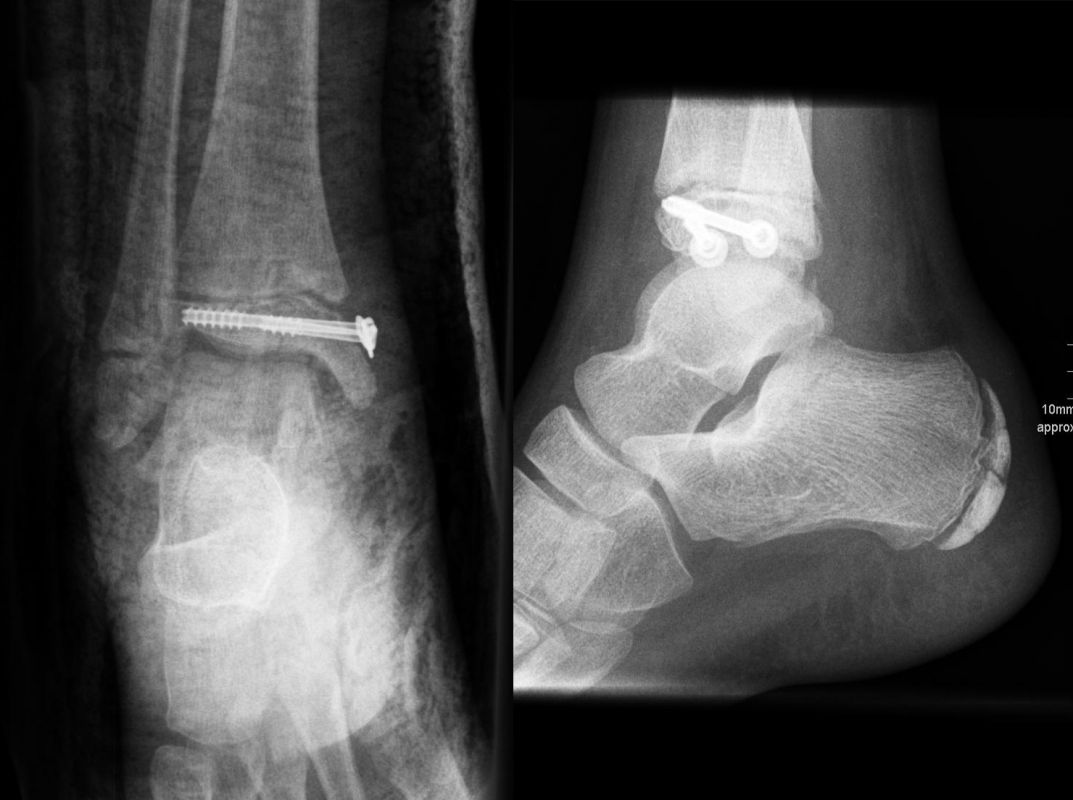

THERAPIE

Behandlungsziel ist die exakte Rekonstruktion der Gelenkfläche sowie die Minimierung des Risikos einer späteren Wachstumsstörung. Dislozierte Frakturen werden offen reponiert, die Osteosynthese erfolgt mit einer Kleinfragmentschraube. Finden sich viele kleine Fragmente kann eine K-Draht Osteosynthese durchgeführt werden. Wird der Innenknöchel operiert, kann bei gleichzeitiger hochgradiger lateraler Instabilität eine Rekonstruktion des lateralen Bandapparats durchgeführt werden. Fibula Frakturen stellen sich meist spontan ein, sodass hier keine zusätzliche Osteosynthese notwendig ist.

Nach der Osteosynthese wird die Fraktur für ca. vier Wochen in einem Unterschenkelgips ruhiggestellt. Bei Schmerzfreiheit der Frakturzone erfolgt anschließend eine schmerzadaptierte Belastungssteigerung über weitere zwei Wochen. Sobald unter Alltagsbedingungen Beschwerdefreiheit besteht kann die sportliche Belastung langsam gesteigert werden. Kirschnerdrähte werden 6-8 Wochen postoperativ, Schrauben nach zwölf Wochen entfernt. Es empfiehlt sich klinische und radiologische Kontrollen im Abstand von 6 Monaten bis zum Wachstumsabschluss durchzuführen, um ein mögliches Fehlwachstum frühzeitig zu erkennen.